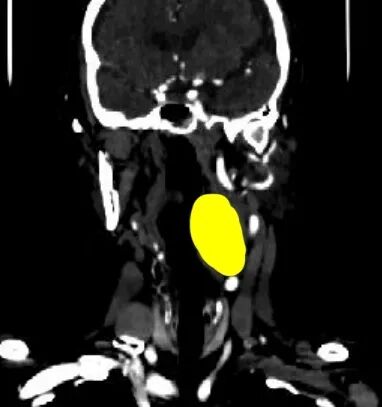

CT扫描中,识别出1个病灶-肿瘤

(根据CT图像,重建了肿瘤、动脉、静脉、大脑、小脑、甲状腺、骨骼、气管、神经等模型)

三维重建中病灶位置信息